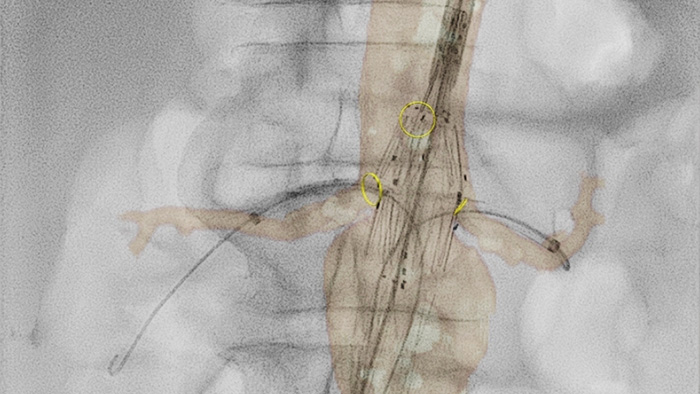

VesselNavigator bietet eine intuitive und fortlaufende 3D Roadmap basierend auf vorhandenen CT-Angiographie- und MRA-Datensätzen, um Sie bei Aorteneingriffen durch das Gefäßsystem zu führen. Eine Studie zeigte eine durchschnittliche Einsparung von 170 ml Kontrastmittel während einer endovaskulären Reparatur eines komplexen Aortenaneurysmas unter Verwendung der Bildfusionsführung mittels CT-Angiographie durch VesselNavigator.1 Eine weitere Studie zeigte eine Reduzierung der durchschnittlichen Behandlungszeit von 6,3 (um 1,1) auf 5,2 Stunden bei FEVAR/BEVAR unter Verwendung der Bildfusionsführung mittels CT-Angiographie durch VesselNavigator.2